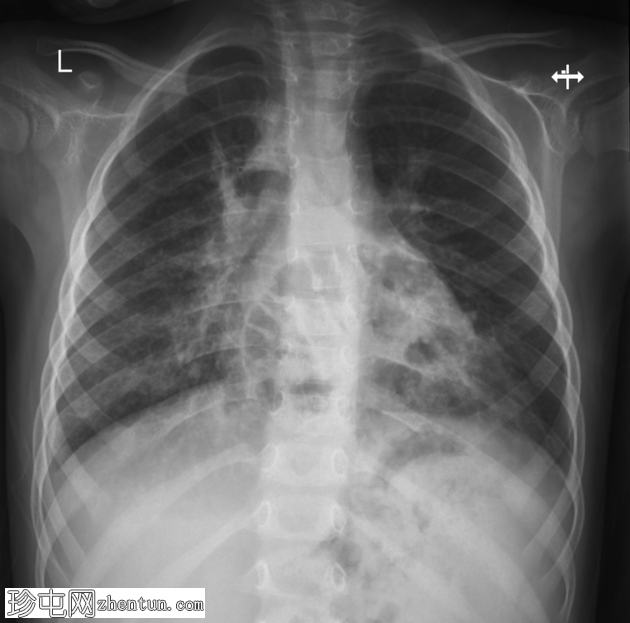

X线片

1.png

正位片

2.png

侧位片

底部可见边界不清的阴影,最符合呼吸道感染的表现。

正位和侧位片上偶然发现胸骨后肠管。